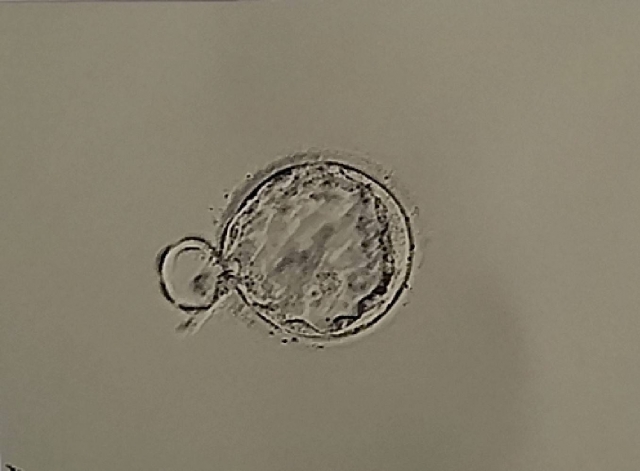

① 受精した卵の力は、ほぼ100%女性のもの

受精直後から胚盤胞へと成長していくのは、卵子のミトコンドリア次第。

卵子には10万~30万個のミトコンドリアが存在します。

肝臓や腎臓、腸など活発な臓器でも1細胞辺り100~2000個といわれていますので、いかに卵子に多いかが分かります。